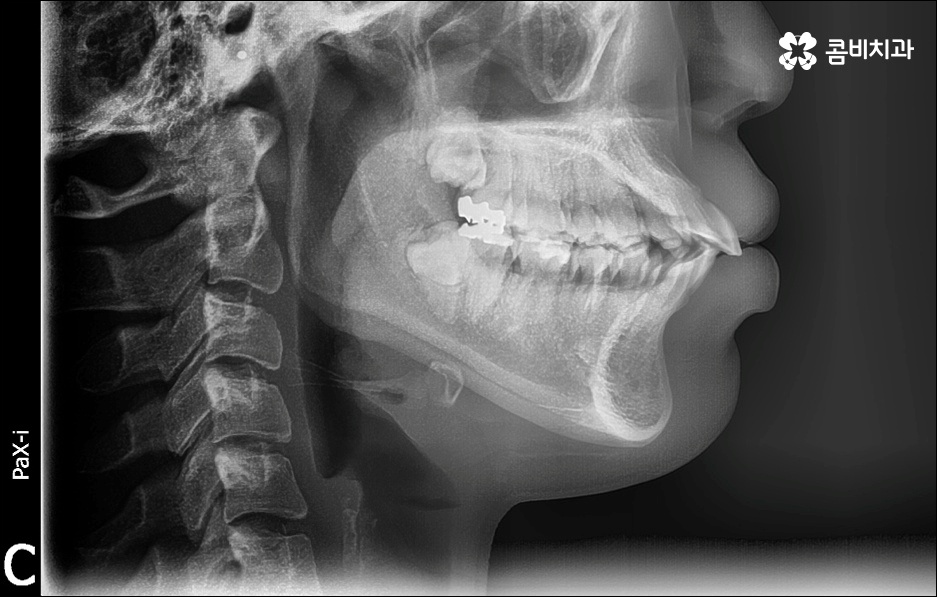

앞니가 튀어나오는 원인은 무엇일까요? 앞니 돌출 의 원인은 치아 크기가 큰 데 반해서 골격이 많이 작거나 상하악골 크기 차이가 많이 나는 것처럼 유전적인 요소에 기인하는 경우가 많으나 후천적인 생활 습관으로 인해서 발생하고 강화될 수도 있기 때문에 주의하실 필요가 있어요. 예를 들어 어릴 때 부터 손톱을 물어뜯거나 손가락을 자주 빠는 습관, 혀로 앞니를 밀면서 빼물곤 하는 습관을 가지고 있었다면 이로 인해 앞니가 튀어나올 수도 있는 거예요. 또한 축농증, 비염 등의 질환으로 인해 구호흡을 하게 되었다면 이것이 원인으로 작용할 수도 있으니 필요하다면 이비인후과와 협진을 하는 등 원인파악과 개선을 전반적으로 함께하시길 권유드리고 있어요.

만약에 앞니 돌출 이 각도만의 문제라면 이를 교정하기 위한 치료는 좀 더 간단하게 끝날 수 있습니다. 말씀드렸던 것처럼 상황에 따라 보다 빠른 부분교정을 통해 앞니만 교정 치료를 진행할 수도 있을 거예요.

하지만 보통은 돌출된 앞니 뿐 만 아니라 골격적인 부분이 원인이 되는 경우가 많으며 이런 경우에는 상태에 맞게 전체적으로 교정을 진행하여야 교합이 올바르게 되고 입매가 전체적으로 균형감 있게 개선될 수 있어요. 이런 경우에 골격적인 원인을 무시한 채 무리하게 치아의 각도만 안쪽으로 넣으려고 하면 자칫 옥니가 될 수도 있기 때문에 이러한 부작용을 막기 위해서도 환자분들의 상황을 정확하게 검진하고 그에 맞는 교정 플랜을 세우는 것이 필요한 거예요. 물론 부정교합 정도가 심각하고 골격적인 원인이 이미 굳어진 경우와 같이 수술이 함께 필요한 케이스도 있을 수 있으나 교정 치료만으로도 튀어나온 앞니가 들어가면서 자연스럽고 부드러운 인상으로 바뀌는 경우도 많으니 먼저 검진과 상담부터 꼼꼼하게 진행해 보시길 권유드리고 있습니다. 특히 개개인의 치열, 교합, 잇몸 상태, 구강구조 등을 면밀하게 파악하고 그에 따른 정확한 치료 계획을 수립할 수 있는 경험 많은 의료진과 함께 하는 것이 중요할 수 있어요.

골격적인 부분이 원인이 되는 경우 치료 시기 역시 중요할 수 있는데요. 성장기가 끝나고 잇몸뼈가 굳어지기 전에 상악과 하악의 균형잡힌 발달을 유도하는 것이 필요하기 때문에 윗턱에 비해 아래턱이 많이 작다면 2차 성징이 나타나기 전에 치료를 시작하는 것이 좋을 거예요. 2차 성장 시기는 성별 (여자 아이가 남자 아이보다 빠름) 및 개인마다 차이가 나지만 보통 10~12세 사이이니 필요하다면 이때 아이와 함께 치과에 내원하시길 추천드리고 있는데요. 돌출입 구조에 있어서 유전의 영향은 30% 정도이니 만약에 부모님께서 상악골이 돌출된 부정교합을 가지고 있다면 더욱 관심을 가지고 아이의 치열을 관찰하셔서 치료 시기를 조율해 보시는 게 좋을 거예요. 또한 상황에 따라 교정 치료 전에 충치나 잇몸을 먼저 치료하는 과정이 필요할 수 있으니 시작 시기나 전체 기간, 방법 등 자세한 사항들에 대해서 면밀한 검진 후 충분하게 상담부터 받아 보시길 권유드리고 있습니다.